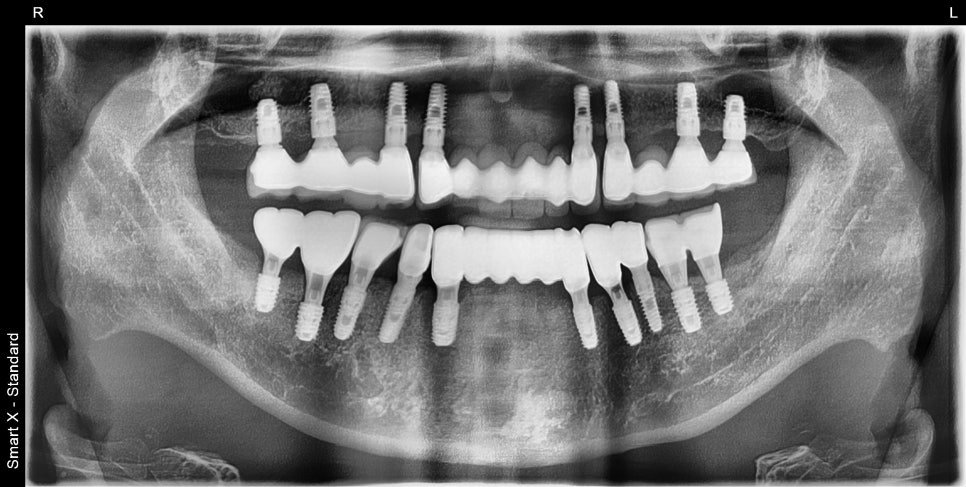

After treatment: X-ray after final prosthesis completion, front and side views

This panoramic X-ray was taken after treatment was completed. The implants had integrated stably and the bite was well adjusted.

Left photo: The upper prosthesis had good overall fixation and the bite was designed to be stable.

Right photo: The final prosthesis was accurately secured to the implant placed in the extracted site.